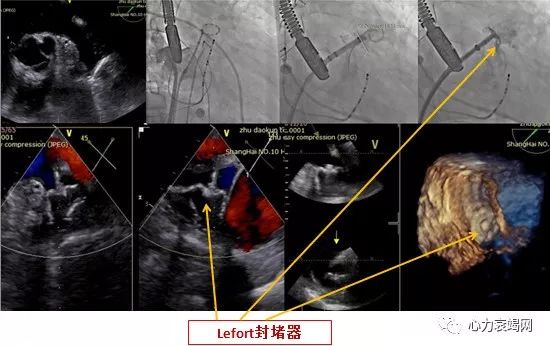

选择28mm*34mm的LAmbre封堵器

术后常规双联抗血小板三个月后,单抗长久

本院第1例左心耳封堵术

术后即刻微量残余分流,直径1mm,提示成功

手术1次释放即成功,总用时90min

术后3月及12月复查TEE提示植入成功,未见残余分流

随访24个月,无严重不良事件发生